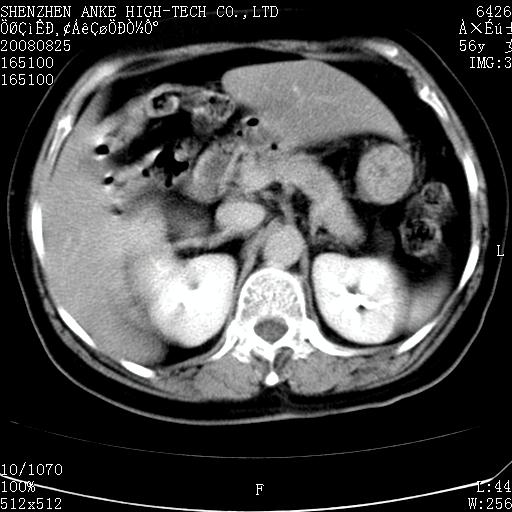

患者,女性,56岁,腰痛3年,查:右腹部约8x10cm肿块,固定,无压痛;8月23日在外院做了平扫,发现右肾巨大肿块(外院具体诊断不祥);今天在我院做了静脉肾盂造影,示:右肾明显增大,分泌功能明显减弱。

1)考虑右肾癌并右肾静脉瘤栓形成。2)脂肪肝。